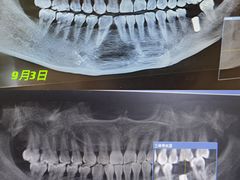

• 劲松口腔医院(蓝色港湾院)

• -劲松口腔医院(蓝色港湾院)

simonaxu | 21-10-10

咩咩 | 21-10-07

【已注销用户】 | 21-10-06